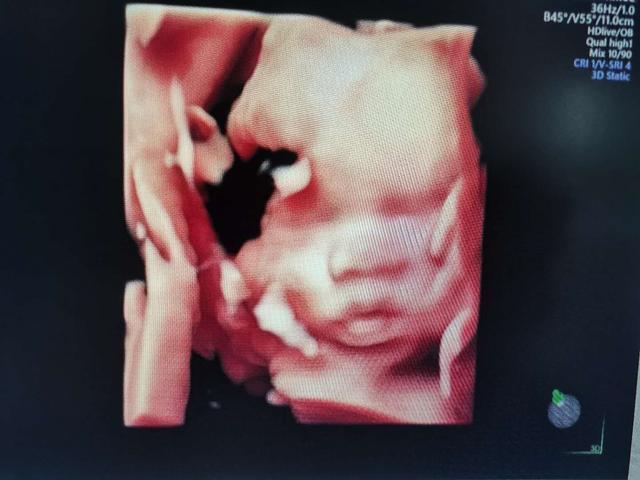

28-32周:是胎儿的小排畸,因为胎儿是一个不断发育完善的过程,需要不断发育不断检查,并不是一次通过就代表以后都没有问题了,不是这样的,这个时期也是给胎儿拍照的好时机,可以看清胎儿的面部成像。四维彩超可以更加清晰立体的看到胎儿的面部表情,拍出来的照片几乎就是宝宝刚出生后的样子,真的很神奇,我们也可以给宝宝留一个相册,这样也能留下一个美好的回忆。